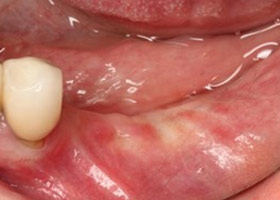

1. 治療前,口內照片;植體外露及牙齦萎縮。